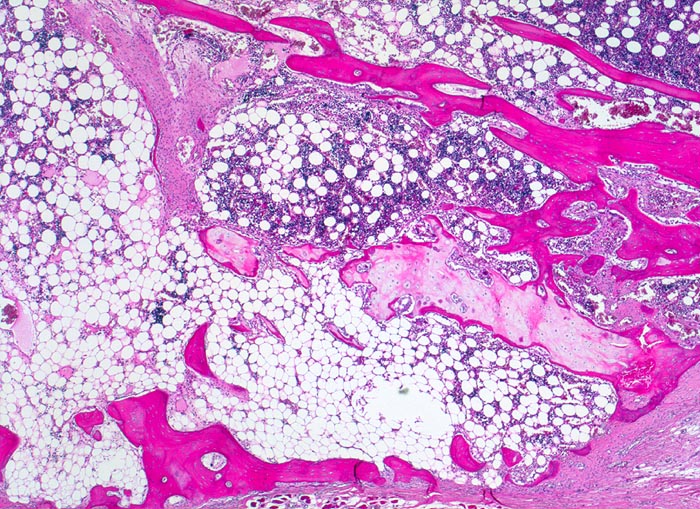

Osteogenesis imperfecta: Frakturkallus

Knochen, Rippe

Frakturkallus bestehend aus metaplastischem Bindegewebe, Knorpelgewebe und Knochengewebe.

Tod an Rechtsherzversagen bei Cor pulmonale. Multiple, zum Teil nicht ganz frische Frakturen vorwiegend der Rippen mit ausgeprägter Deformierung des Thorax und des übrigen Skeletts. Generalisierte Osteopenie. Kyphoskoliose. Multiple Knochenmarkembolien der Lunge.

Glasknochenkrankheit, pulmonale arterielle Hypertonie